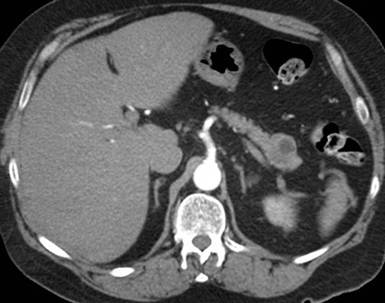

Radiological follow-up was obtained in 2011, when the patient was admitted for left sided abdominal pain again. A CT was performed and confirmed diverticulitis. This showed that the lymphoepithelial cyst in the pancreatic tail was unchanged in size and appearance (Figure 4) The benefit of follow-up imaging over three years later confirmed the correct diagnosis from the EUS-FNA. The patient recovered following a course of antibiotic therapy for the diverticulitis and has now been discharged from clinical follow-up.

Figure 4. Three year follow-up CT in 2011 demonstrates no change in size or appearance of the lymphoepithelial cyst. Unfortunately, the CTs were obtained in different phases and therefore these are the only CT images available. The initial diagnosis of an lymphoepithelial cyst was confirmed on the follow-up CT using size criteria. |